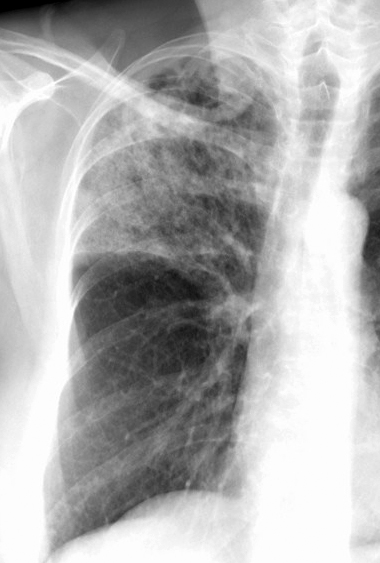

Case 17 Pneum with abscess PA